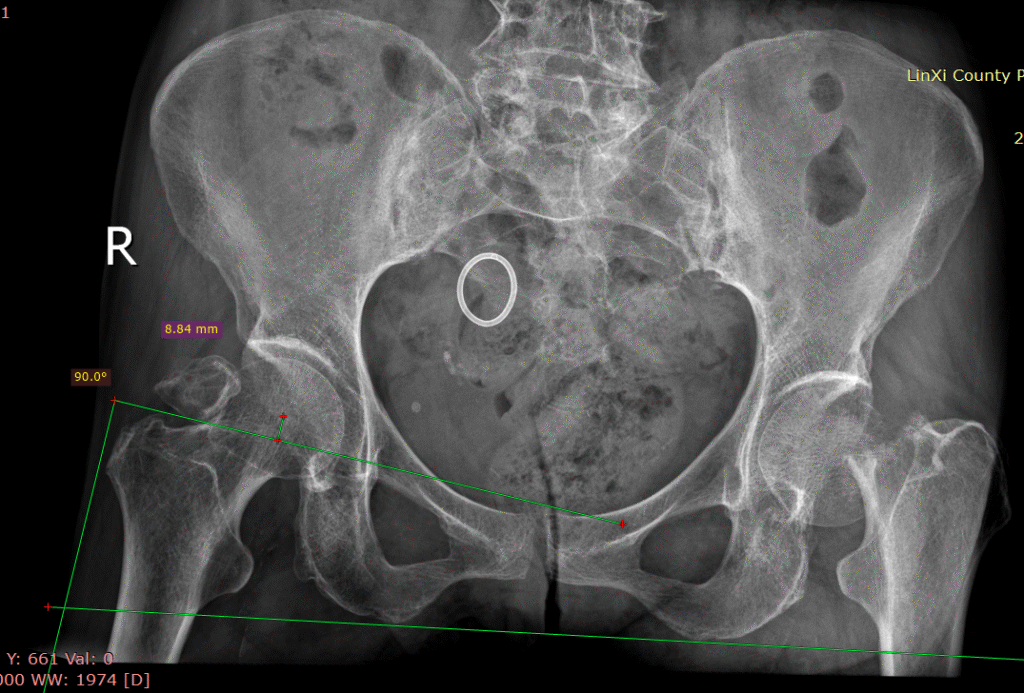

股骨颈骨折人工股骨头置换术(Artificial femoral head replacement for femoral neck fractures)